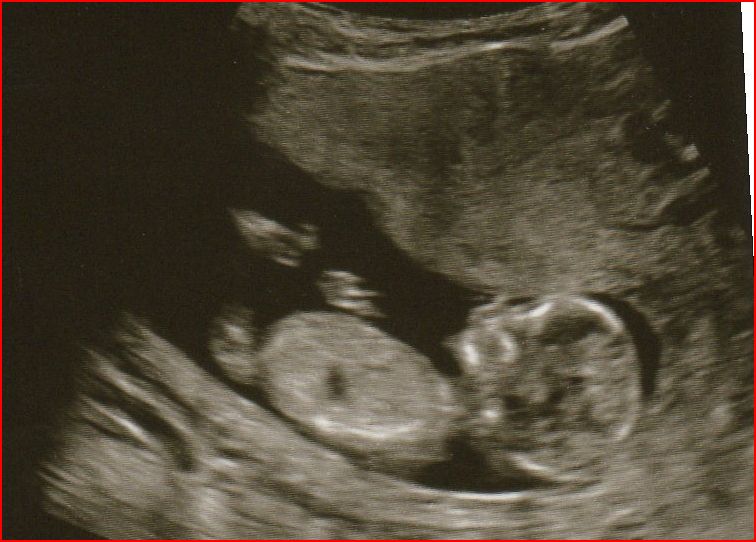

Its looking like the whole thing is one large image on the post and i can't find out how to enlarge it, although it looks like the third pic may have a nub

Never mind hope you don't mind but i worked out how to do it. Thinking that may be a nub and it look pretty flat at that gestation. Have uploaded the pic on this post in case it helps you get more guesses.

Ok hope you don't mind but i blew the others up to, whilst i was sticking my nose in, just in case it helps you get any more guesses :happy:

Attachment 7649